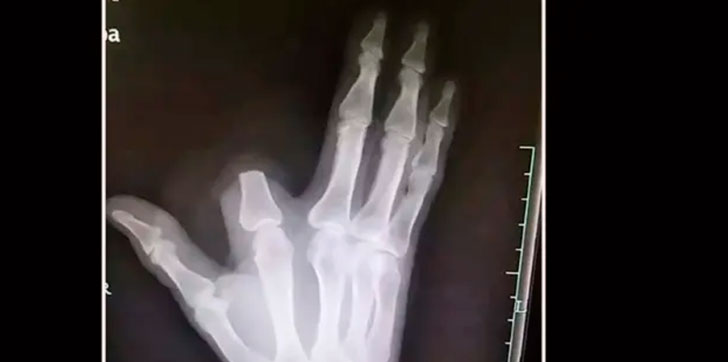

CHINA.- Un hombre en China estaba cortando leña cerca de su pueblo en las montañas del distrito Shangyu de la provincia de Zhejiang cuando una serpiente lo mordió en el dedo índice de su mano derecha.

Rápidamente y al creer que se trataba de una Deinagkistrodon acutus, cuya mordedura podría ser fatal, el hombre tomó la decisión de cortarse el dedo antes de que el veneno pudiera extenderse al resto del cuerpo. En esta zona de China se tiene la creencia de que esta serpiente tiene un veneno tan poderoso que no podrás caminar más de 5 pasos antes de morir.

Dicho esto, y tras cortarse el dedo, el hombre envolvió su mano en una tela y se dirigió 80 kilómetros al hospital más cercano para recibir tratamiento, dejando lo que creía que era un dedo inútil en la ladera de la montaña. Sin embargo, como ha explicado finalmente el médico que lo atendió a varios medios locales:

Cuenta el propio médico que si el hombre hubiese llevado el dedo podrían haberlo salvado. Los doctores explican que cuando se trata de una mordedura, la herida no se debe manipular. Recomiendan “no usar torniquetes ni cortar, chupar o escarificar la herida o aplicar productos químicos o descargas eléctricas, y en su lugar se debe buscar atención médica inmediata, moviendo el área afectada lo menos posible”, zanjan.